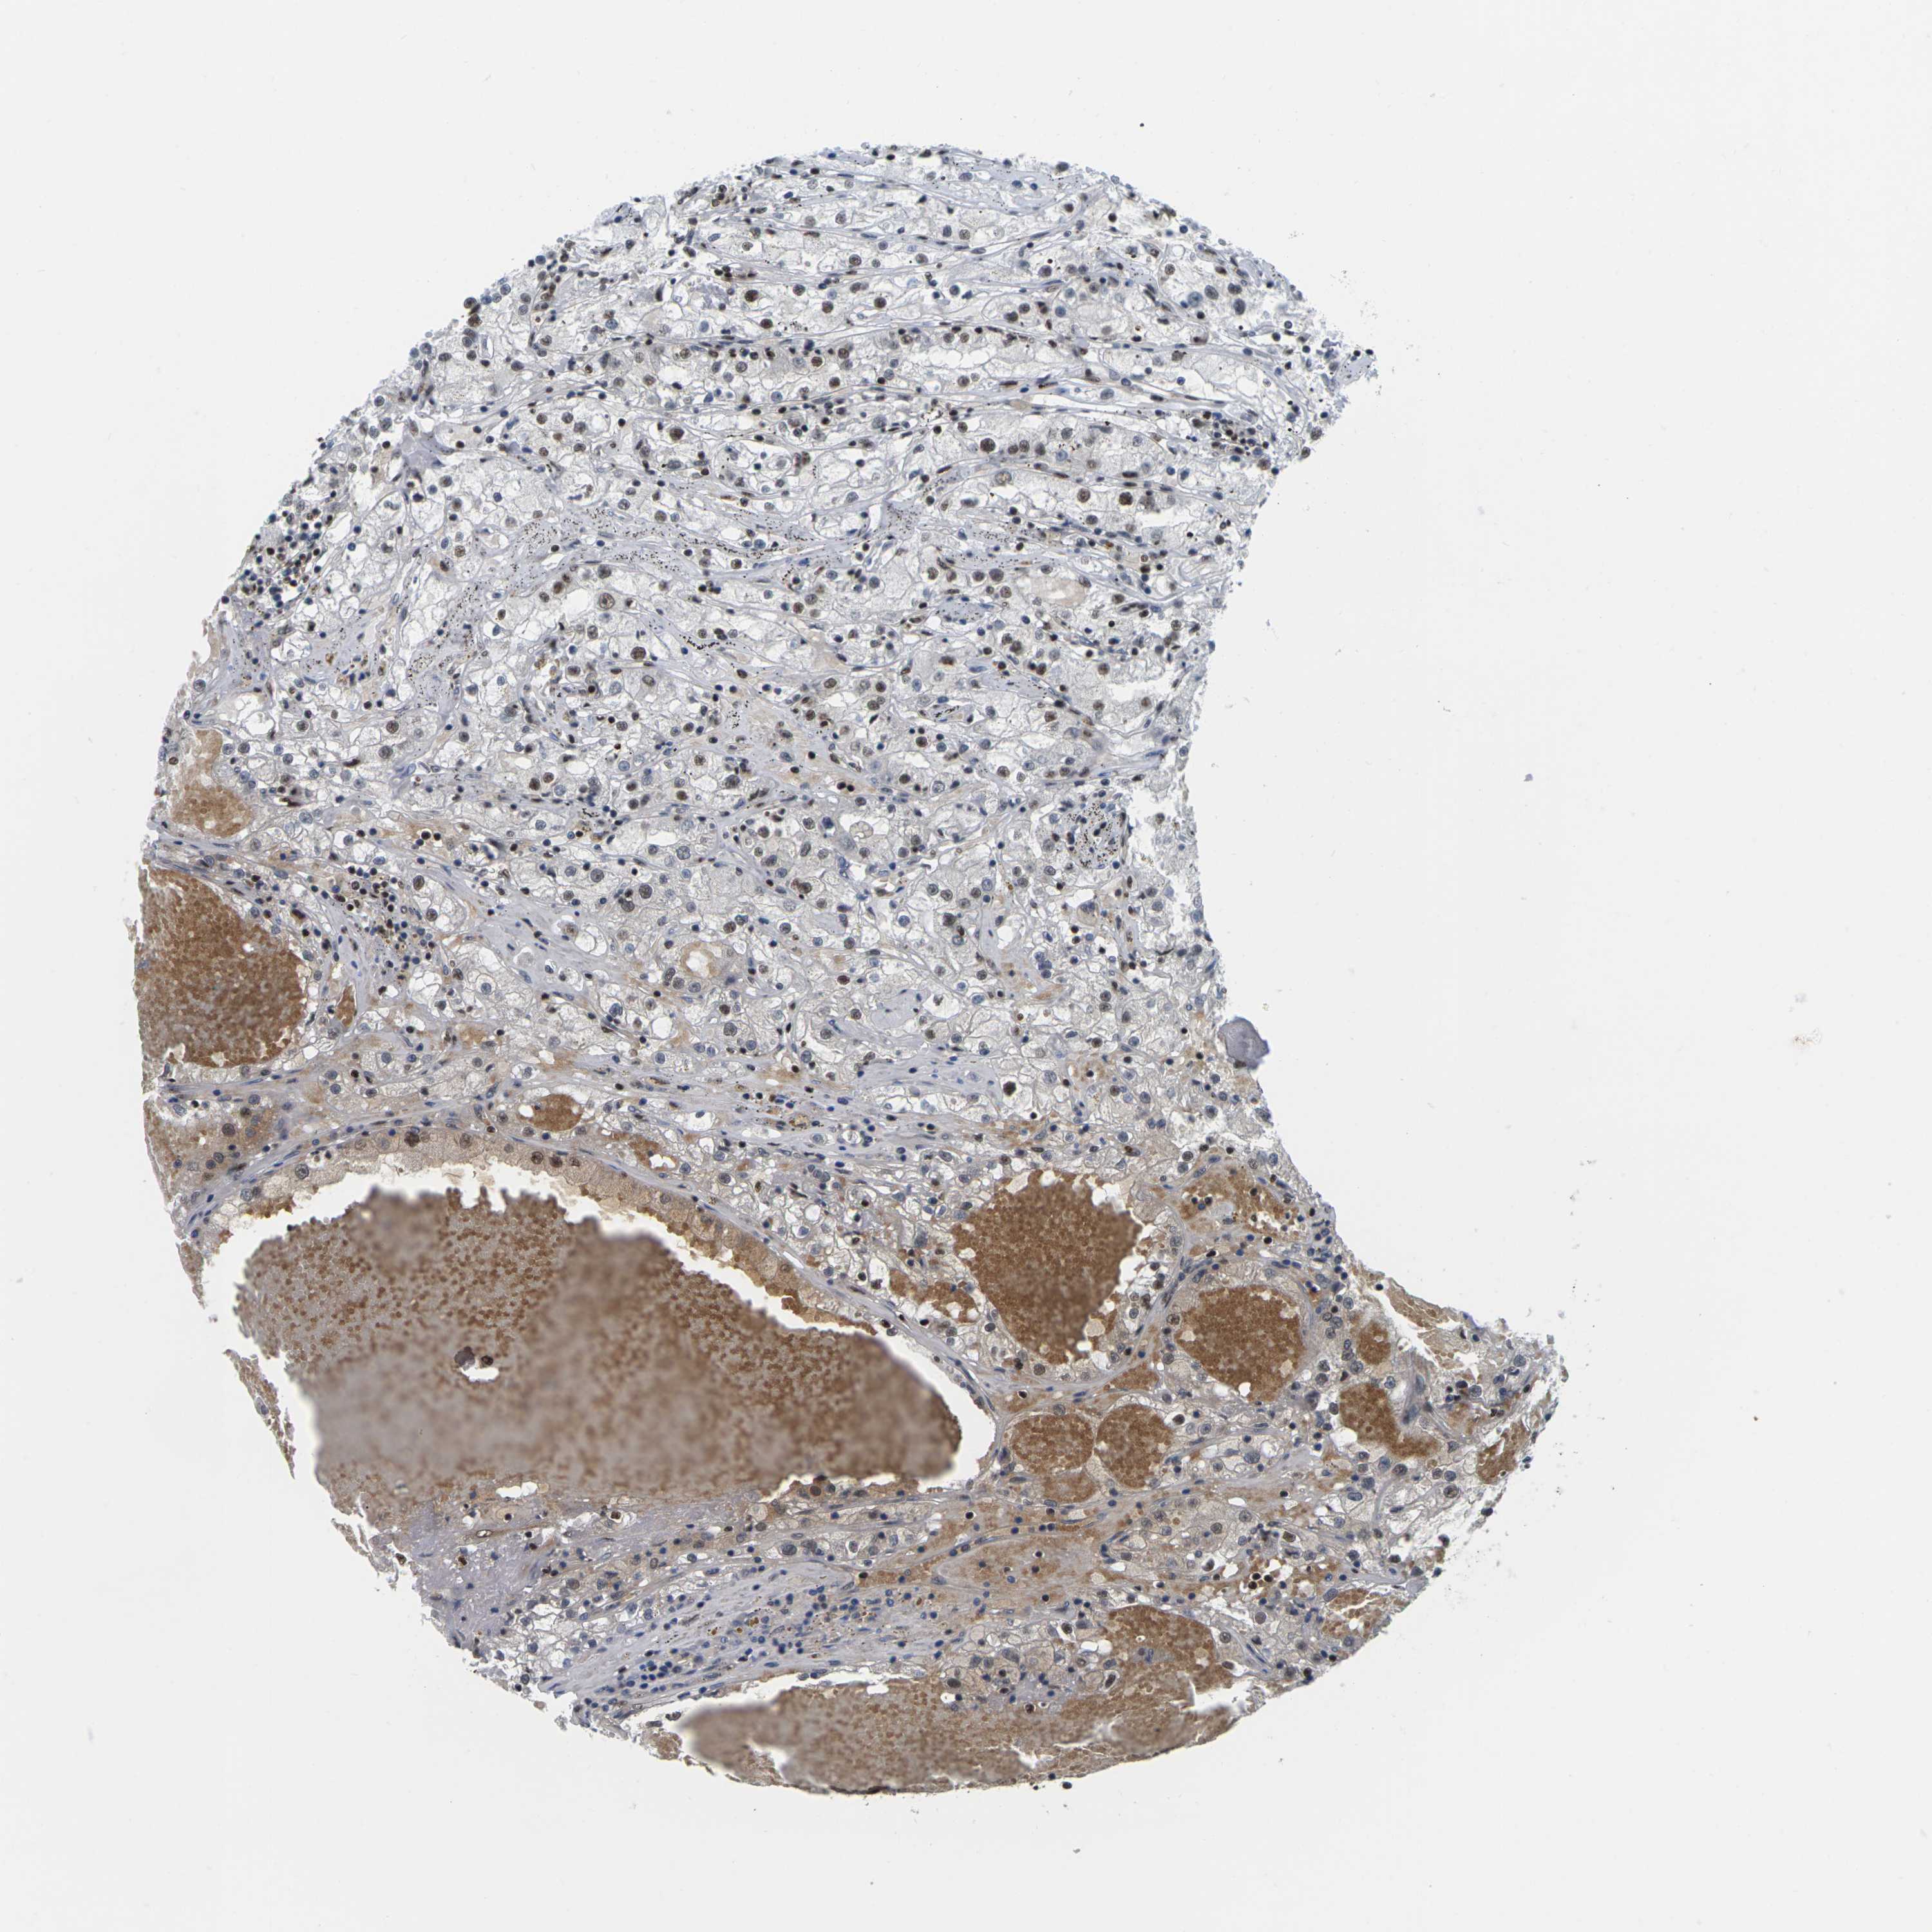

KIDNEY RENAL CLEAR CELL CARCINOMA (VALIDATION) - Interactive survival scatter ploti

The Survival Scatter plot shows the clinical status (i.e. dead or alive) for all individuals in the patient cohort, based on the same data that underlies the corresponding Kaplan-Meier plots. Patients that are alive at last time for follow-up are shown in blue and patients who have died during the study are shown in red.

The x-axis shows the expression levels (FPKM) of the investigated gene in the tumor tissue at the time of diagnosis. The y-axis shows the follow-up time after diagnosis (years). Both axes are complimented with kernel density curves demonstrating the data density over the axes. The top density plot shows the expression levels (FPKM) distribution among dead (red) and alive patients (blue). The right density plot shows the data density of the survived years of dead patients with high and low expression levels respectively, stratified using the cutoff indicated by the vertical dashed line through the Survival Scatter plot. This cutoff is automatically defined based on the FPKM cutoff that minimizes the p-score. The cutoff can be changed by dragging the vertical line or by entering a cutoff value in the square labeled "Current cut-off".

Under the Survival Scatter plot the p-score landscape (black curve; left axis) is shown together with dead median separation (red curve; right axis). Dead median separation is the difference in median mRNA expression between patients who have died with high and low expression, respectively. It is calculated as follows: median FPKM expression of dead patients with high expression - median FPKM expression of dead patients with low expression. This is intended to aid the user in visually exploring custom cutoffs and the associated p-scores and dead median separation.

Individual patient data is displayed and can be filtered by clicking on one or more of the category buttons on the top of the page. Categories describing expression level and patient information include: high, low, alive, dead, female, male and tumor stages. The scale of the x-axis can be toggled between linear and log-scale by clicking on the "x log" button. Mouse-over function shows TCGA ID, patient information and mRNA expression (FPKM) for each patient.

& Survival analysisi

Kaplan-Meier plots summarize results from analysis of correlation between mRNA expression level and patient survival. Patients were divided based on level of expression into one of the two groups "low" (under cut off) or "high" (over cut off). X-axis shows time for survival (years) and y-axis shows the probability of survival, where 1.0 corresponds to 100 percent.

MAGOH is not prognostic in Kidney Renal Clear Cell Carcinoma (validation)

Best expression cut offi

Based on the FPKM value of each gene, patients were classified into two groups and association between prognosis (survival) and gene expression (FPKM) was examined. The best expression cut-off refers the FPKM value that yields maximal difference with regard to survival between the two groups at the lowest log-rank P-value. Best expression cut-off was selected based on survival analysis .

When clicking on this number, the vertical dashed line indicating cut-off, the interactive survival plot, and the Kaplan-Meier curve will be adjusted to show results based on the best expression cut-off.

: 59.69

TCGA RNA samplesi

RNA-seq data is reported as average FPKM (number Fragments Per Kilobase of exon per Million reads), generated by the The Cancer Genome Atlas (TCGA) .

Normal distribution across the dataset is visualized with box plots, shown as median and 25th and 75th percentiles. Points are displayed as outliers if they are above or below 1.5 times the interquartile range. FPKM values of the individual samples are presented next to the box plot.

Average pTPM 73.3

Number of samples 100